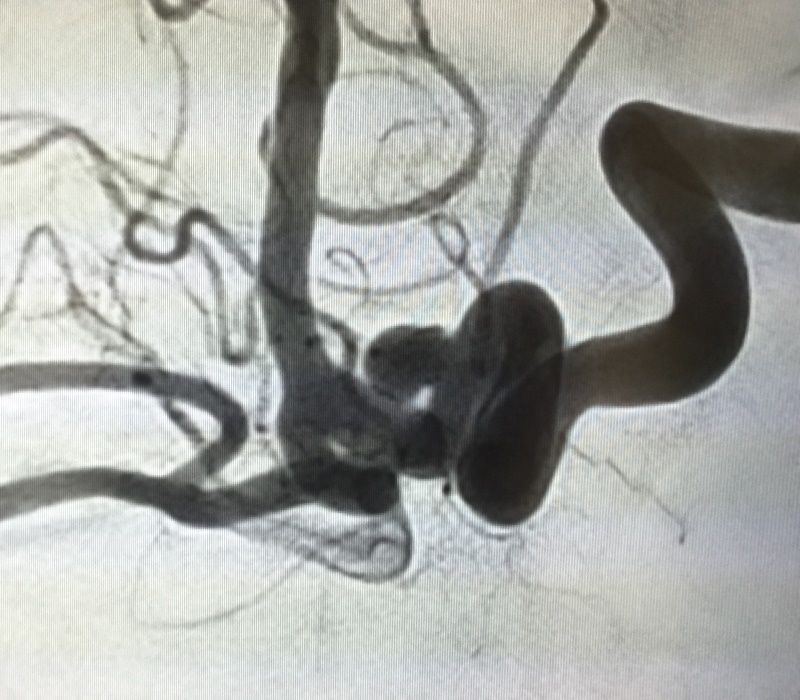

¿Quieres ver un quirófano híbrido por dentro?

Entramos al quirófano híbrido con angiógrafo plano, uno de los más avanzados, cuyo uso está indicado para operaciones de gran precisión como las aneurismas

La impresión 3D, también aplicada en cirugía cerebral

El tratamiento de un aneurisma cerebral se sirvió de una réplica de la circulación de la zona realizada por impresión 3D